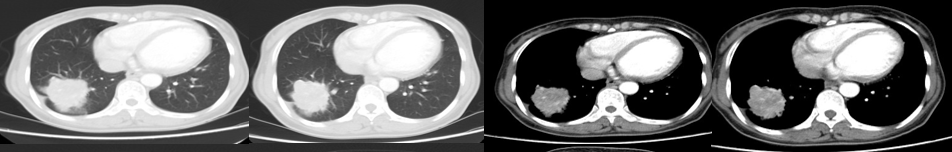

影像学及疗效评价:患者治疗期间定期复查胸部CT,右肺原发灶大小分别为4.7×3.8cm(2周期后)、5.2×4.1cm(7周期后)、3.4×3.2cm(8周期后,与放疗关系大),提示患者对化疗疗效差病灶变化如图2-2所示。

图2-2 治疗期间胸部CT动态变化

影像学及疗效评价:患者治疗期间定期复查胸部CT,右肺原发灶大小分别为2.6×2.5cm(2020年5月11日,疗效评价为PR)、2.6×2.1cm(2020年8月16日,疗效评价为持续PR)、2.6×2.2cm(2020年11月12日,疗效评价为持续PR),后期(2020年12月26日及2021年3月2日病灶略有增大,但大小无法测量,疗效评价为持续SD)。

图2-3 二线治疗期间胸部CT动态变化